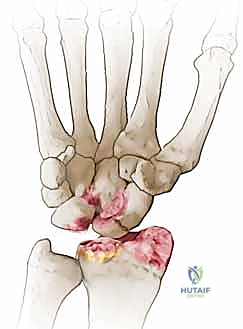

لفهم طبيعة متلازمة SNAC والعملية الجراحية، يجب علينا أولاً الغوص في التركيب التشريحي المذهل لمفصل الرسغ. يتكون الرسغ البشري من ثماني عظام صغيرة تُعرف بعظام الرسغ (Carpal bones)، مرتبة في صفين (صف قريب وصف بعيد).

العظم الزورقي (Scaphoid Bone) هو العظم الأهم والأكثر تعقيداً في هذه المجموعة. يعمل هذا العظم كجسر رابط ومحور ارتكاز بين الصفين القريب والبعيد لعظام الرسغ. هذا الموقع الاستراتيجي يجعله عرضة لضغط ميكانيكي هائل أثناء حركات اليد اليومية، ولكنه في الوقت نفسه يجعله الأكثر عرضة للكسور.

المشكلة الكبرى التي تواجه العظم الزورقي تكمن في التروية الدموية (Blood Supply). الدم يدخل إلى العظم الزورقي من الجزء البعيد (Distal pole) ويتجه نحو الجزء القريب (Proximal pole) في اتجاه عكسي (Retrograde). لذلك، عند حدوث كسر في منتصف العظم، ينقطع الدم عن الجزء القريب، مما يؤدي إلى عدم التئام الكسر (Nonunion) وفي كثير من الأحيان موت العظم (Avascular Necrosis).

متلازمة SNAC (Scaphoid Nonunion Advanced Collapse) هي حالة تدهور تدريجي ومأساوي لمفصل الرسغ. تبدأ القصة بكسر في العظم الزورقي (غالباً بسبب السقوط على يد ممدودة). إذا لم يتم تشخيص هذا الكسر أو لم يلتئم بشكل صحيح، فإن العظم الزورقي ينقسم إلى قطعتين تتحركان بشكل غير طبيعي ومستقل عن بعضهما البعض.

هذه الحركة غير الطبيعية تخلق احتكاكاً مستمراً (Micro-trauma) مع العظام المجاورة، وتحديداً عظم الكعبرة (Radius). بمرور الوقت (أشهر أو سنوات)، يؤدي هذا الاحتكاك إلى تآكل الغضاريف الناعمة التي تغطي العظام، مما يسبب خشونة مفصلية شديدة (Osteoarthritis).